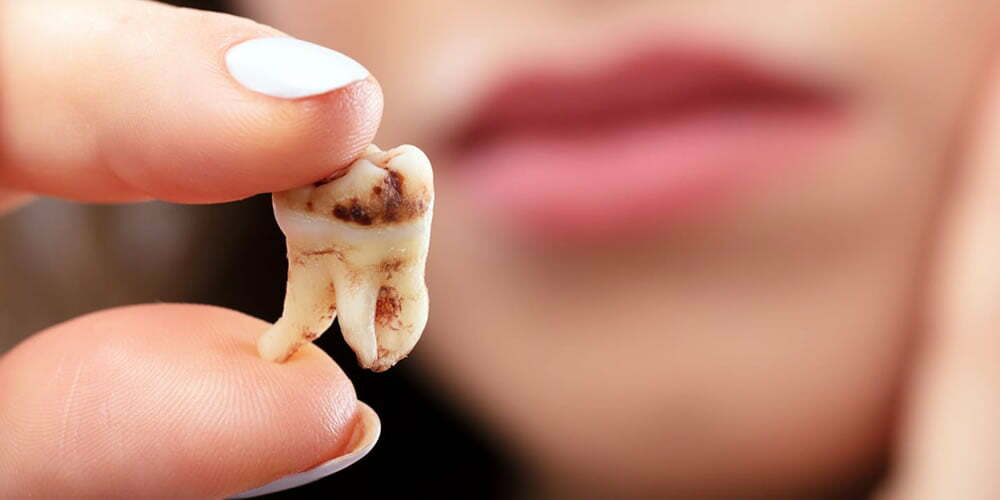

Tedavilerimiz

Tedavilerinizi gönül rahatlığıyla gerçekleştirebileceğiniz bir ortam sizi bekliyor.